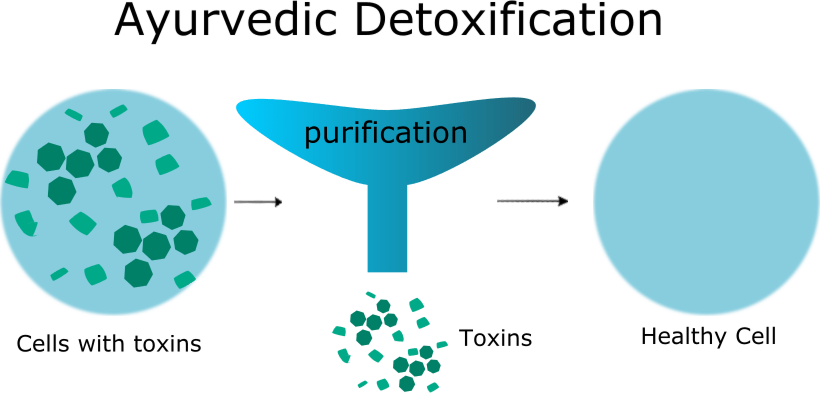

Ayurvedic psoriasis treatment can help to identify the root cause of psoriasis through Ayurvedic diagnostic tools and correct the abnormal changes that have occurred in the body. Various ayurvedic treatments are used to treat psoriasis, depending on the severity of the disease. The cleansing process or detoxification helps to restore the body’s normal physiological functions, and medications help heal psoriasis.

It is explained as how a cleaned cloth gets colored easily, in the same manner, if one undergoes purificatory procedures or panchakarma treatments (shodana chikitsa’s) like therapeutic vomiting (Vamana), therapeutic purgation (Virechana), or therapeutic bloodletting (Raktasravana), the elevated doshas get eliminated from the body and then the timely administration of internal medications will help to cure psoriasis.

Repeated purificatory procedures will help eliminate the toxic materials from the body, and the purified body that receives medications acts effectively to cure the disease. Detoxification corrects the abnormal functions of the cells, so that cell function becomes normal.

Detoxification is a part of Ayurvedic psoriasis treatment.

Repeated detoxification (Shodana) helps to keep the body free from accumulating toxins. It also helps to create a healthy environment inside the body for better absorption of the medicines.

Yes, detoxification is needed in ayurvedic psoriasis treatment as psoriasis is a chronic disease that may not respond to medication unless it is purified. Panchakarma treatments or purification help to eliminate toxic substances from the body, clear the channels, and correct the digestive system. Medicines consumed after purification act quickly and efficiently.